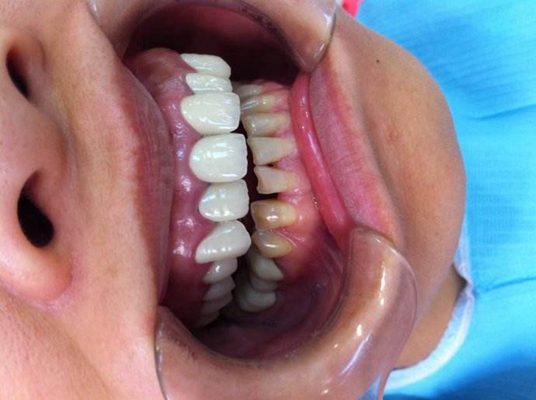

牙齦炎圖片

牙齦炎和牙周炎